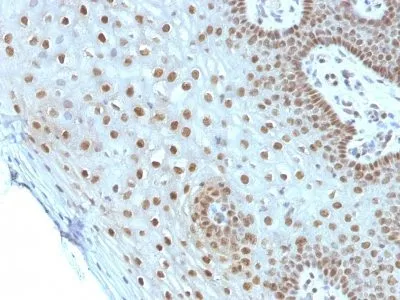

Anti-c-Myc(MYC275)

Anti-c-Myc(MYC275)

- Applications: IHC, FFPE (verified)

- Validated Applications: IHC, FFPE

- Positive Control: HL-60 cells or breast carcinoma

- Additionnal Information: Immunohistology formalin-fixed 1-2 ug/mL|Staining of formalin-fixed tissues requires boiling tissue sections in 10 mM Tris with 1 mM EDTA, pH 9.0, for 10-20 min followed by cooling at RT for 20 minutes|Flow Cytometry 0.5-1 ug/million cells/0.1 mL|Immunofluorescence 1-2 ug/mL|Optimal dilution for a specific application should be determined by user